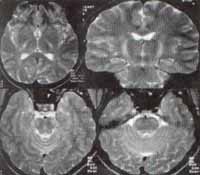

Inicia su sintomatología a los 29 meses, al presentar inestabilidad en la bipedestación y lateralidad en la marcha, luego de caer de una altura de más o menos 50cms con posterior trauma en región occipital, sin pérdida de conocimiento y sin ninguna otra sintomatología asociada. No hay exposición a tóxicos o ingesta accidental de algún medicamento. No antecedentes de infecciones previas al evento. Por anterior sintomatología se inicia estudio realizándose tomografía axial computarizada (TAC) que descartó colecciones hemorrágicas peri, subdurales o intraparenquimatosas, hematomas que pudieran estar presentes secundarios al trauma, pero reveló hipodensidad de la sustancia blanca de ambos hemisferios cerebrales. El paciente se deja hospitalizado, persistiendo ataxia sin otros signos neurológicos, por lo cual se decide realizar resonancia magnética nuclear (RMN) de cráneo la cual ratificó lo evidenciado ya en la TAC, mostrando marcada y extensa alteración en la intensidad de la señal de la sustancia blanca de manera difusa comprometiendo las regiones frontal, parietal, temporal, occipital y así como ambos hemisferios cerebelosos siendo hipointensa en T1 e hiperintensa en T2, en relación con proceso crónico. Se evidencia además, atrofia del tallo cerebral y mesencéfalo, en relación con proceso crónico descrito, leucodistrofia. Tras anteriores hallazgos se realizan estudios complementarios citoquímicos de líquido cefalorraquídeo normal al igual que el estudio bioquímico del nivel de la aril sulfatasa A.

Figura 1: Aumento de la intensidad de la sustancia blanca en forma difusa.